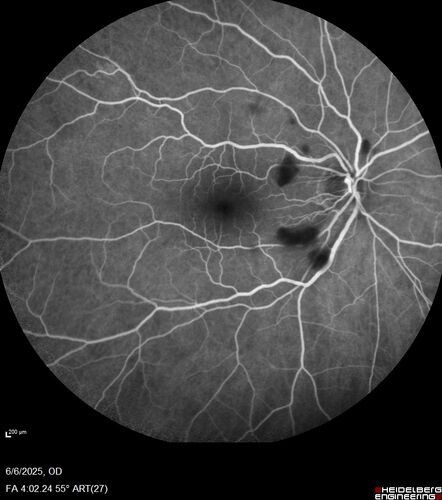

Cotton Wool Spots following cardio-pulmonary bypass

The patient had emergency thoracotomy about 3 weeks ago he had an aortic dissection with a root aneurysm. It had dissected down to the iliacs. The patient had a thoracotomy and aortic valve replacement and large aortic graft.